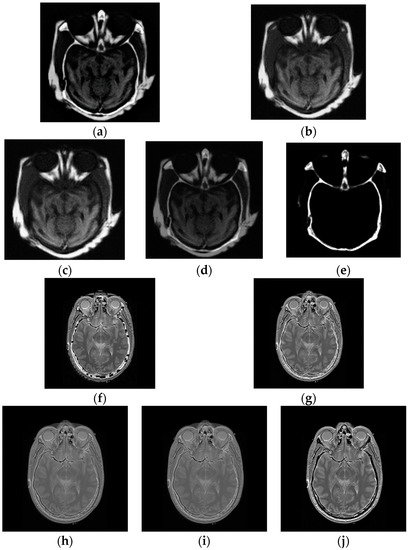

Figure 2.

Multi-modal images, (a) CT and (b) MRI images.

4.3. Multi-Modal Image Fusion

In multi-modal tests, the original images shown in Figure 2 are applied to generate the fused images. The fusion experiments are performed on these images using CP, PCA, DCT, LP and the average methods, and the corresponding fused results, displayed in Figure 6a–e, show the fused results for two original images in Figure 2a using five algorithms, together with Figure 6f–j giving the fused images of the two input images shown in Figure 2b.

The final fused images should both include the information of the two original images. Nonetheless, in the first test of the multi-focus images, the fused image in Figure 6e by CP fusion algorithm almost only consists of the information of the CT image and hardly includes the information of the MR image. The fused results obtained by PCA and DCT are similar, and only provide the information of the MR image instead of the CT image. The LP fusion method illustrates the information of the CT image and also displays the MR information. Likewise, for the fusion experiments of the two original images given in Figure 2b, the fused image acquired via the CP algorithm only exhibits the MR information and does not obtain the information from the CT image.